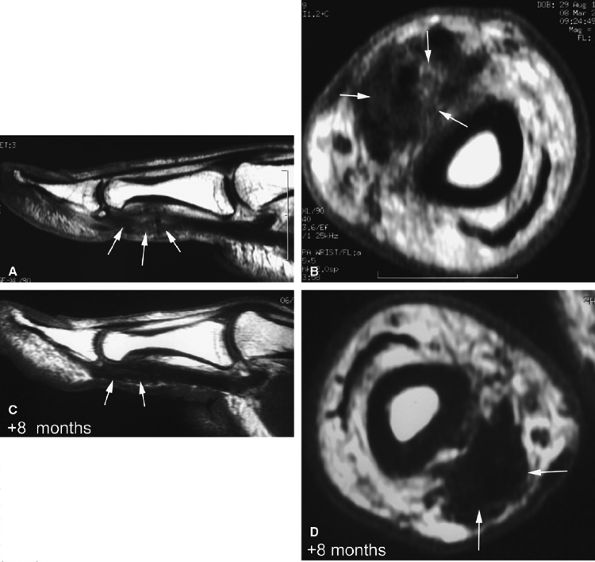

FIGURE 11.52 ● Elongation of a tendon callus of the flexor pollicis longus. Sagittal (A) and axial (B) post-contrast T1-weighted images show a thickened callus 1 cm in length with predominant scar tissue (arrows). Eight months later, sagittal (C) and axial (D) post-contrast T1-weighted images demonstrate the maturation process with thinning of the callus and predominant low-signal-intensity mature tissue (arrows).